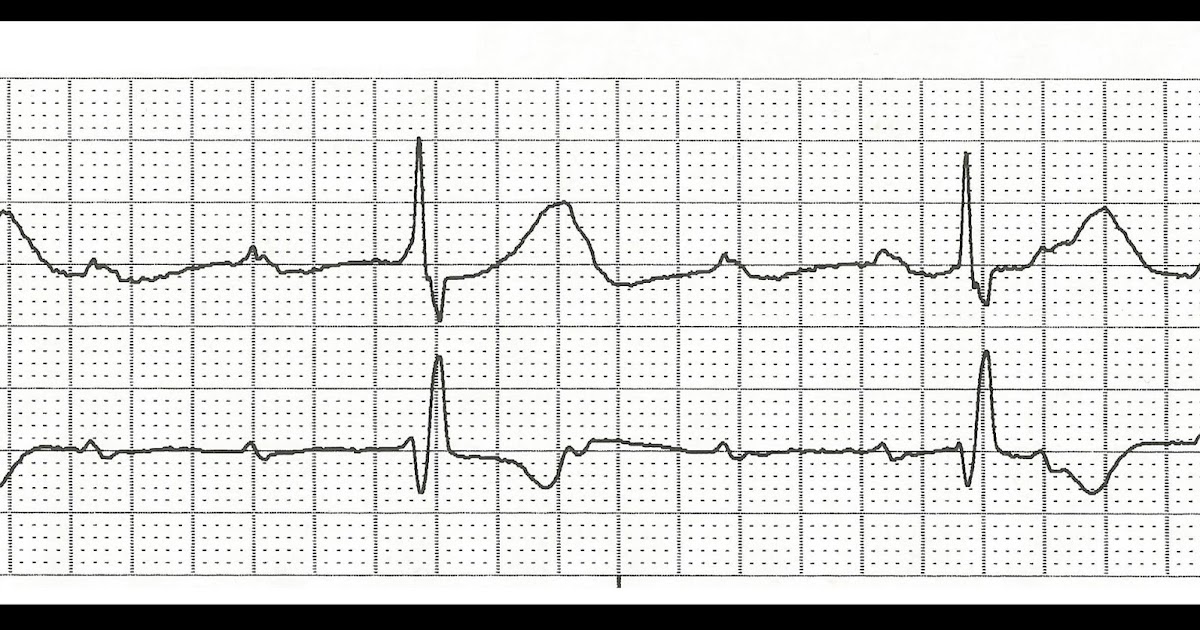

Heart Block Ecg Practice . Web this ekg practice test is designed to help you learn to recoginze all of the ekg rhythms that you will encounter. Web ecg features of complete heart block. Web with our ekg strip practice drills, it is easy to engage in fast, interactive learning. Pr interval > 200ms (five small squares) there is delay, without interruption, in conduction from atria to ventricles. Severe bradycardia due to absence of av conduction. Web this ekg rhythm practice quiz will test your knowledge on the different types. Web ekg practice learn with flashcards, games, and more — for free. This interruption of impulse transmission results in characteristic ecg The ecg demonstrates complete av dissociation,. Web atrioventricular (av) block (often referred to as “heart block”) involves the partial or complete interruption of impulse transmission from the atria to the ventricles. This page provides an introduction to heart block rhythms with links to our lessons and drills.

The ecg demonstrates complete av dissociation,. Web ecg features of complete heart block. This interruption of impulse transmission results in characteristic ecg This page provides an introduction to heart block rhythms with links to our lessons and drills. Web with our ekg strip practice drills, it is easy to engage in fast, interactive learning. Web atrioventricular (av) block (often referred to as “heart block”) involves the partial or complete interruption of impulse transmission from the atria to the ventricles. Pr interval > 200ms (five small squares) there is delay, without interruption, in conduction from atria to ventricles. Web this ekg practice test is designed to help you learn to recoginze all of the ekg rhythms that you will encounter. Web this ekg rhythm practice quiz will test your knowledge on the different types. Severe bradycardia due to absence of av conduction.

ECG Rhythms Advanced Heart Block Heart Block Ecg Practice The ecg demonstrates complete av dissociation,. Pr interval > 200ms (five small squares) there is delay, without interruption, in conduction from atria to ventricles. Web atrioventricular (av) block (often referred to as “heart block”) involves the partial or complete interruption of impulse transmission from the atria to the ventricles. Severe bradycardia due to absence of av conduction. Web this ekg. Heart Block Ecg Practice.

ECG Rhythms Complete Heart Block or Not? Heart Block Ecg Practice Web ekg practice learn with flashcards, games, and more — for free. The ecg demonstrates complete av dissociation,. Web ecg features of complete heart block. Web this ekg rhythm practice quiz will test your knowledge on the different types. Severe bradycardia due to absence of av conduction. Web atrioventricular (av) block (often referred to as “heart block”) involves the partial. Heart Block Ecg Practice.

ECG Rhythms Is this Complete Heart Block? Heart Block Ecg Practice This page provides an introduction to heart block rhythms with links to our lessons and drills. Web with our ekg strip practice drills, it is easy to engage in fast, interactive learning. Web atrioventricular (av) block (often referred to as “heart block”) involves the partial or complete interruption of impulse transmission from the atria to the ventricles. Web ecg features. Heart Block Ecg Practice.

Complete (3°) Heart Block EKG RK.MD Heart Block Ecg Practice Web this ekg rhythm practice quiz will test your knowledge on the different types. This interruption of impulse transmission results in characteristic ecg Web with our ekg strip practice drills, it is easy to engage in fast, interactive learning. Web ecg features of complete heart block. Pr interval > 200ms (five small squares) there is delay, without interruption, in conduction. Heart Block Ecg Practice.